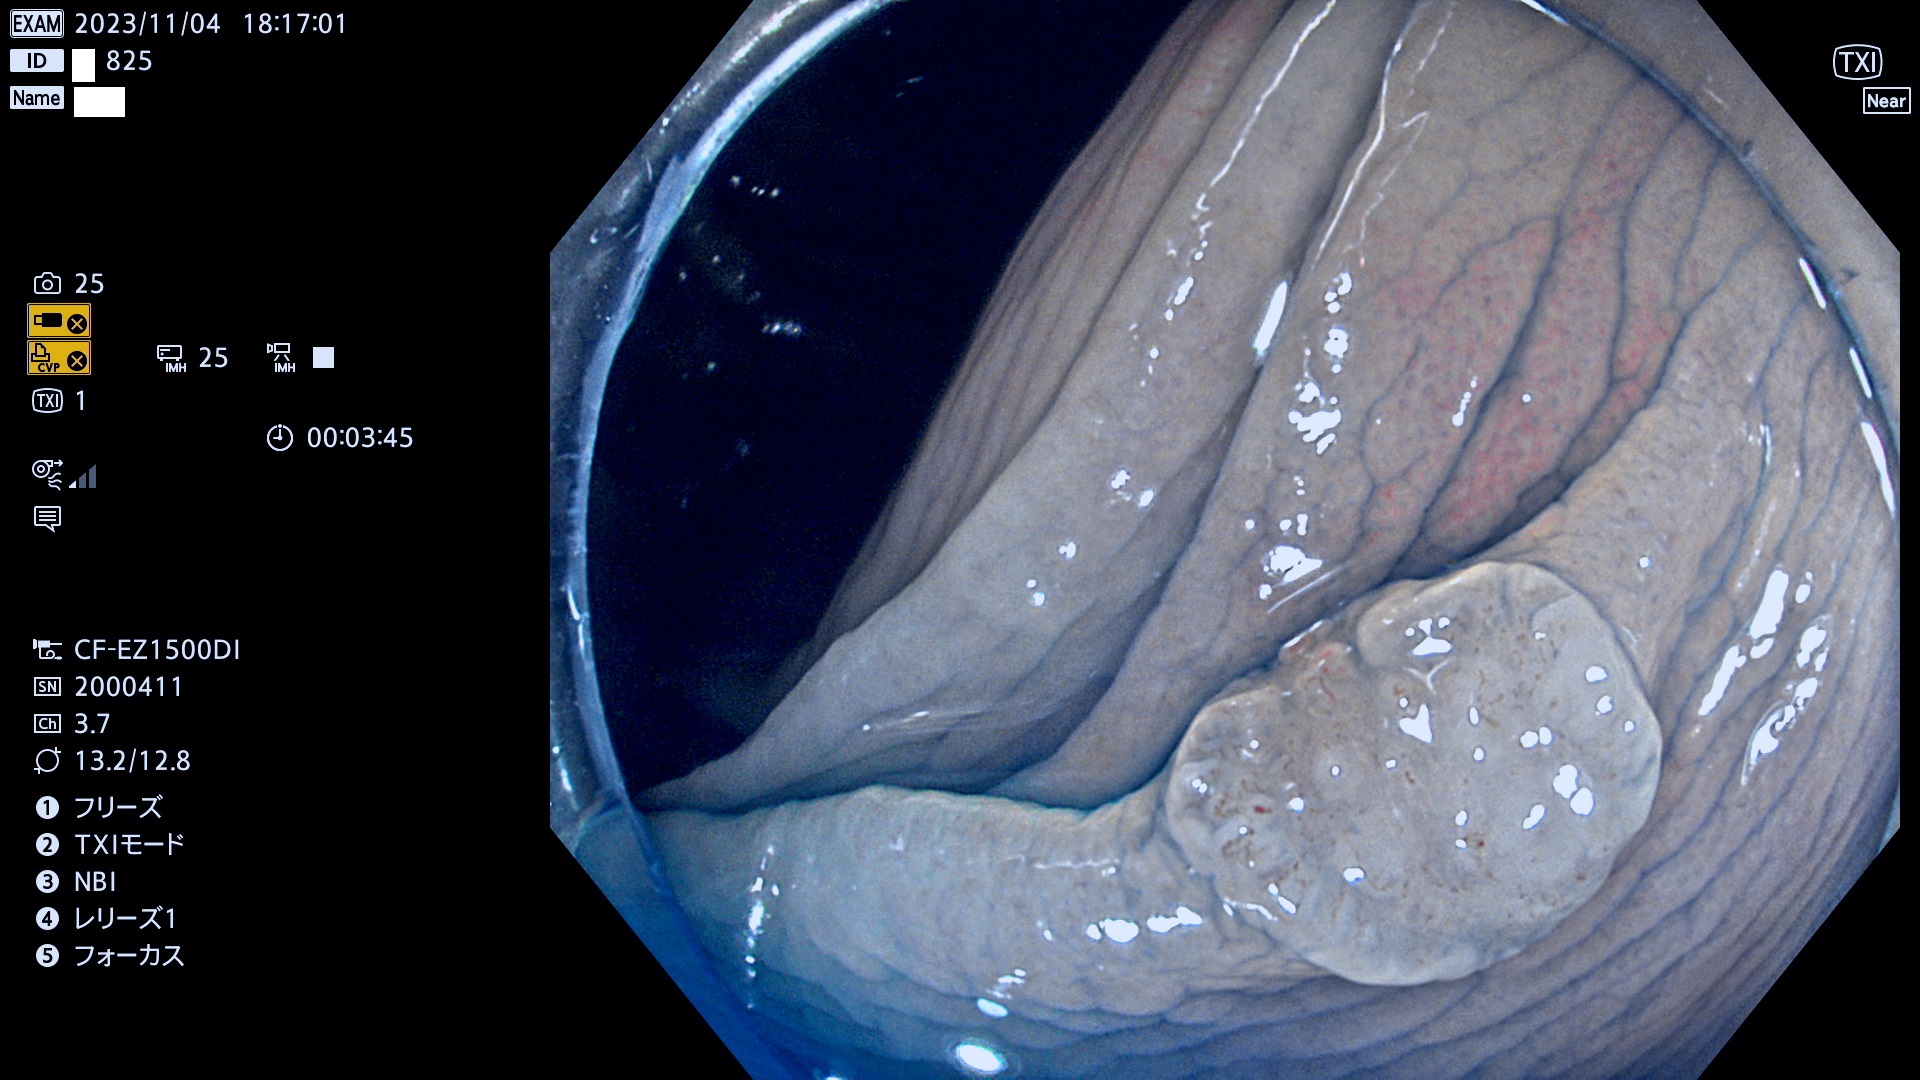

今週のUb、Uc型腺腫

表面型腺腫(Flat Adenoma)の中で、完全に平坦な物をUb、陥凹している物をUcと呼びます。平坦隆起型(Ua)よりも、発見が難しく危険な病変です。このタイプは「内視鏡後・大腸癌の重要犯人」であり、この発見率は「腺腫発見率」よりも、重要な意味があります。

毎週の検査(木・金・土・日)に発見されたUb、Uc型・腺腫を、その週の日曜の夜にUPし1週間、提示します。

抽出の対象期間 2023年11月2日(木)〜11月6(月)の5日間(60件の検査)11件